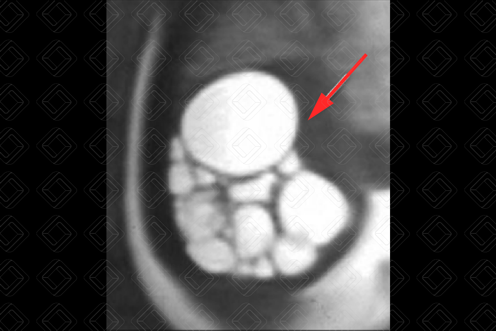

Texto alternativo para a imagem Figura 1. Créditos: Dra. Elazir Mota - Rio de Janeiro/RJ

Texto alternativo para a imagem Figura 2. Créditos: Dra. Elazir Mota - Rio de Janeiro/RJ

Descrição das figuras 1 e 2: Ressonância magnética fetal - sequência ponderada em T2 apresentando múltiplas formações ovaladas com hipersinal em T2 (setas vermelhas), compatível com cistos, não comunicantes e de tamanhos variados na loja renal esquerda. Observe ausência de parênquima renal adjacente. Achados muito sugestivos de rim multicístico displásico esquerdo.

• Ressonância magnética do abdome: E sse exame é muito útil para avaliação intra-útero quando a ultrassonografia fetal não consegue definir com exatidão o aspecto de imagem. Na ressonância magnética fetal, observam-se múltiplas imagens císticas, com hipersinal em T2, com tamanhos variados e não comunicantes (setas vermelhas) (figuras 1 e 2).